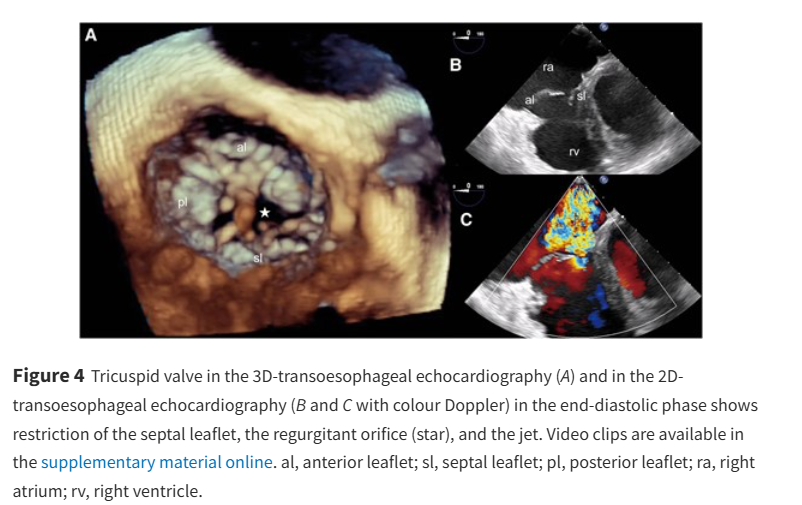

A not so straightforward case of atrial fibrillation and flutter - what was the role of the tricuspid valve? doi.org/10.1093/ehjcr/… #EHJCaseReports Philipp Sommer Tee Joo YEO Aaysha Cader Boldizsar Kovacs Erik Rafflenbeul A.Nazmi Calik Obayda Azizy Sara Moscatelli EHJCaseReports Editor-in-Chief #CardioX #EPeeps